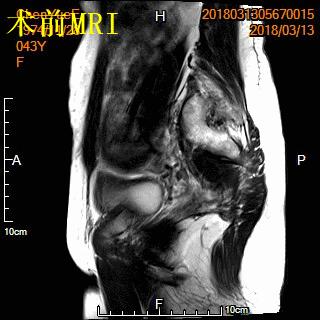

中年女性,发现子宫肌瘤进行性增大5年余。复查彩超提示多发肌瘤,较前明显增大(最大者直径近10cm)。近半年尿频、尿急症状进行性加重,考虑增大的子宫肌瘤压迫膀胱所致。

- MRI检查显示显示多发子巨大宫肌瘤,压迫膀胱。

MRI显示多发子巨大宫肌瘤,压迫膀胱